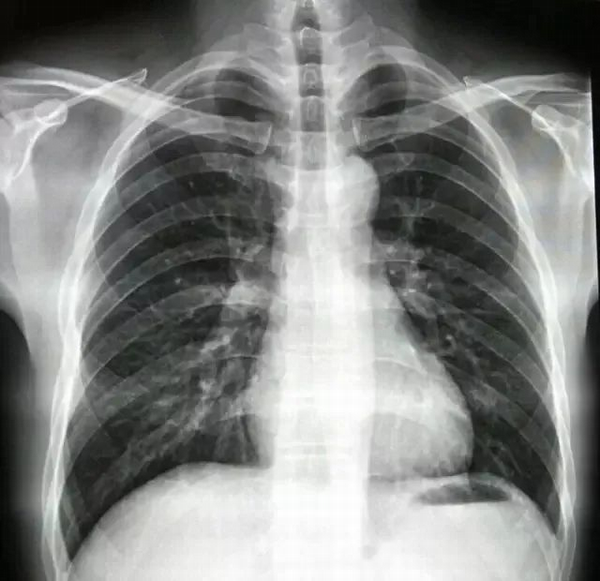

圖1是一個正常女性患者的胸部正位片。這是去除了胸罩拍的標準的片子,我們看到的肺野沒有異物。雙肺、心臟及骨頭都顯示很清楚。